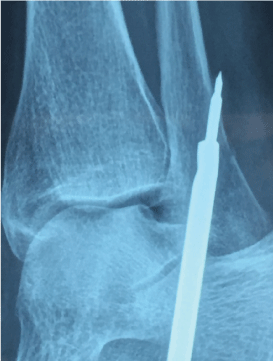

The proximal fixation of the allograft is performed through a fibular tunnel done at the ATL insertion level by using a guide introduced under fluoroscopic guidance, distally to proximally, with a forward-backwards angle of 60 degrees and a minimal length of 3 cm. At this time it is necessary to separate the peroneal tendons so they are not injured with the guide point when emerging through the bone posterior cortical, preferably with a Homans separator or a narrow periosteum scrapper, located through a 0.5 cm incision. Once the guide point is located, a 4 mm cannulated drill is used to make a tunnel of at least 2 cm in length where the fibular part of the free tendon will be resting. The tunnel depth within the tendon is marked and introduced by pulling the free ends until the titanium bottom anchors in the posterior cortical of the fibula (Figure 4).

Figure 4: Proximal tunnel. View Figure 4